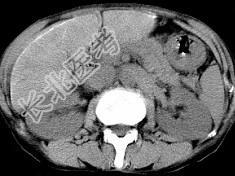

- 单项选择题男,40岁有血吸虫感染史, 腹胀不适,食欲减退, CT扫描所见如图,最可能的诊断是 ( )

A、肝炎后肝硬化

B、血吸虫后肝硬化

C、酒精性肝硬化

D、胆汁性肝硬化

E、脂肪肝